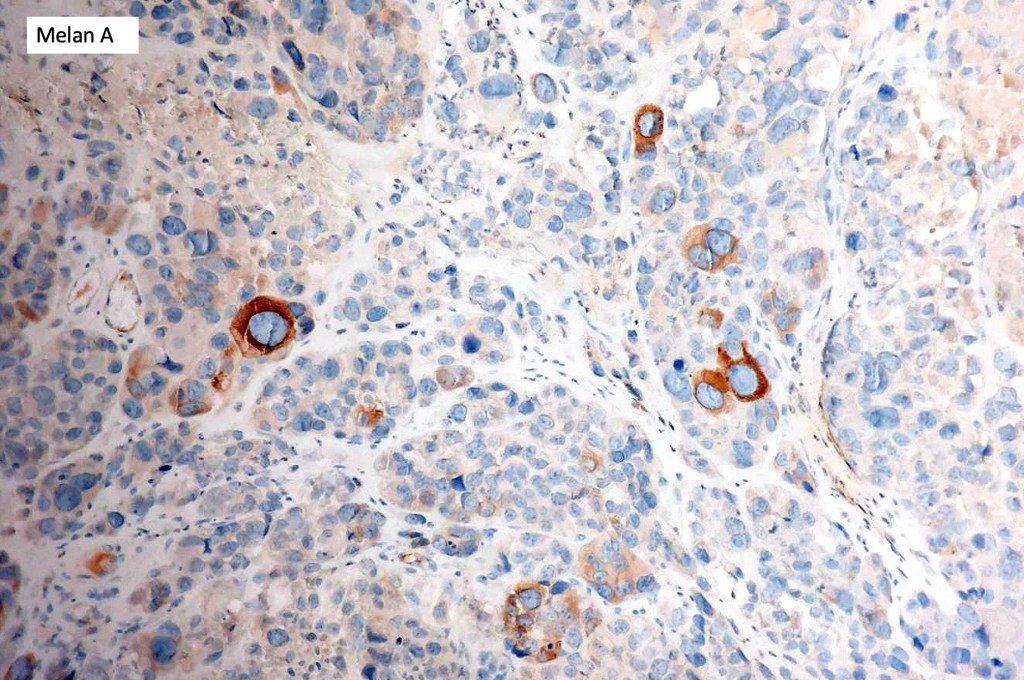

These are very rare variants of amelanotic or virtually amelanotic melanoma where a primary melanoma or a metastasis shows partial (DN) or complete loss (UN) of recognizable histological and immunohistochemical features. The histology may lead the pathologists to consider lymphoma, sarcoma, anaplastic carcinoma or a small cell tumor. Some examples of rhabdoid melanoma & melanoma with heterologous differentiation probably belong in this category. Ultimately, if there is no identifiable/recognizable primary tumor, diagnosis may only be comfortably made with next-generation sequencing. In the cases presented below, immunohistochemistry was of value in determining the melanoctic nature of the tumor (undifferentiated melanoma).